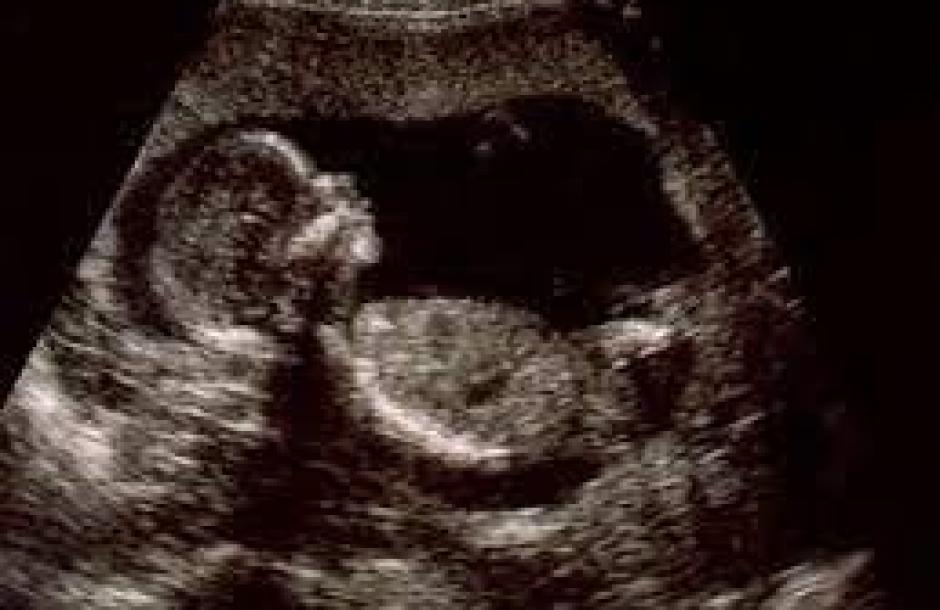

صدمت امرأة في الثمانينات من عمرها الأطباء عندما اكتشفوا أن آلام البطن التي تشكو منها هي في الحقيقة جنين محنط برحمها منذ قرابة 4 عقود.

وذكرت صحيفة "ديلي ستار" البريطانية أن المرأة البالغة 84 عاما ذهبت إلى عيادة الصحة العامة بسبب ألم في بطنها، وتبين أنها تحمل جنينا محنطا منذ 40 عاما.

ويعتقد الأطباء أن الجنين تعرض للتكلس داخل الرحم، في حدث نادر للغاية يسمى "الجنين المتحجر" أو "الجنين المتكلس".

وتحدث هذه الحالة عندما يموت الجنين في رحم أمه، ويكون كبيرا حيث لا يمكن للجسم امتصاصه، فيتكلس من الخارج مما يحمي جسم الأم من الأنسجة الميتة للجنين ويقيها من العدوى.

ويعتقد الأطباء أن الطفل مات وتحنط في الأسبوع الأربعين من الحمل، وأن السيدة لم تتلقَ الرعاية المناسبة في أثناء فترة الحمل.